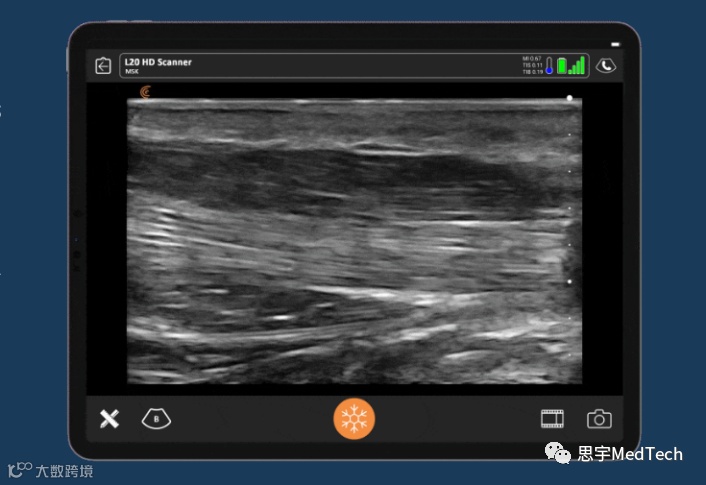

Clarius Mobile Health致力于开发便携式无线超声系统,在方便、低成本的同时,使用户能够在手机上获取超声图像。Clarius手持式无线超声扫描仪可与iOS和安卓设备相连,提供传统上只有体积较大的高端系统才能提供的高分辨率超声图像。Clarius超声扫描仪在全球90多个国家有售。

Zura手持式血流动力学超声系统与由Clarius提供技术支持的ClariTEE经食道回声探头构成配套设备。它们是第一个也是唯一一个先进的手持式血流动力学管理平台,用于实时决策,照顾最危险的病人。手持超声机的迷你体积在空间有限的ICU中也是一个关键优势。Zura手持机与Clarius超声应用一起操作,该应用可与苹果和安卓智能设备无线连接。此外,该系统成本低廉,医院能以一个推车式系统的成本购买多个Zura手持式系统。